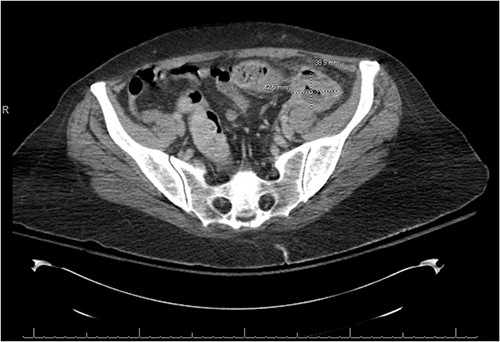

There was a suspicion of underlying abdominal infection causing her altered mental status given the presence of abdominal pain and low grade fever. A computed tomography (CT) scan of the chest, abdomen and pelvis was completed to assess for prior or current malignancy. Acute on chronic sigmoid diverticulitis with a left colo-ovarian fistula and a 4.3 cm left adnexal abscess was found (Figs 1 and 2); yet, no evidence of malignancy was noted. Antibiotic therapy was initiated, and interventional radiology was consulted for abscess drainage. Cancer antigen (CA)-125 and carcinoembryonic antigen (CEA) were only mildly elevated and attributed to generalized inflammation.

A fistulous connection from the sigmoid colon to the ovary is suggested. A dotted line arrow points out the connection.

There is a thick-walled enhancing, 3.9 × 4.3 × 4.2 cm3 perisigmoidal collection containing nondependent gas and fluid with adjacent inflammatory fat stranding, suggestive of tubo-ovarian abscess.